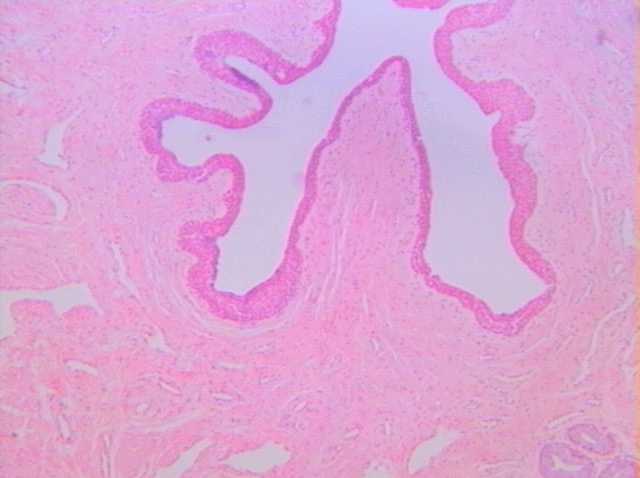

尿道腔

尿道上皮

(複層立方上皮)

尿道海綿體

尿道旁腺

切片位置:雄性尿道(海綿體部前段)

切片倍率:100x

染色方式:h&e stain

低倍下(100x)之雄性海綿體部尿道切片,位置在海綿體部之前段。此區域之上皮組織位於由接續之前尿路系統的移形上皮轉換而成與尿道開口處之體表複層鱗狀上皮之過渡性區域,因而呈現複層立方狀。